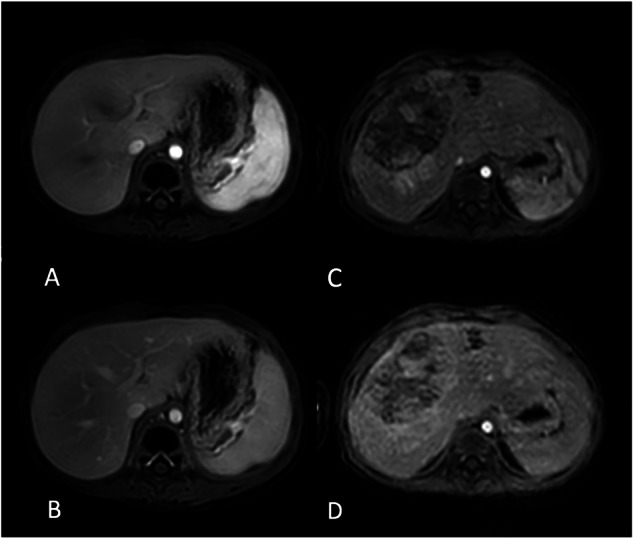

{"title":"Innovative 4D FreeBreathing technique in pediatric abdominal MRI improves feasibility and image quality.","authors":"Patricia Tischendorf, Laura Beck, Tobias Krähling, Jan H Lange, Walter Heindel","doi":"10.1007/s00330-025-11577-2","DOIUrl":null,"url":null,"abstract":"<p><strong>Objectives: </strong>To compare the feasibility and imaging quality of a golden angle radial stack-of-stars dynamic three-dimensional free-breathing T1w turbo field echo acquisition (4D FreeBreathing) with a conventional dynamic cartesian breath-hold T1w sequence in young children undergoing abdominal magnetic resonance imaging (MRI).</p><p><strong>Materials and methods: </strong>Fifty consecutive pediatric patients (34 females; 3.4 ± 2.0 years) underwent abdominal MRI: 25 were examined with 4D FreeBreathing and 25 with conventional dynamic T1w sequence. The image quality was evaluated subjectively on a 5-point scale by two radiologists. Interobserver agreement, as well as signal-to-noise ratio for arterial (SNRart) and portal venous (SNRpv) phases, were evaluated separately. Additionally, the image quality of 4D FreeBreathing sequence was compared to a non-dynamic post-contrast radial stack-of-stars free-breathing T1w fast field echo acquisition (3D T1w Vane mDixon). Interobserver agreement of both assessors was calculated using quadratic weighted Cohen's kappa test (ϰ), while independent samples Student's t-test was employed to compare mean SNR values among the two groups.</p><p><strong>Results: </strong>Using 4D FreeBreathing, SNRart and SNRpv were significantly higher from 500 ± 170 and 550 ± 160 to 900 ± 210 and 820 ± 260 (p < 0.001); the diagnostic image quality increased from 77.6 to 89.6%; respiratory artifacts decreased from 22.4 to 10.4%, with an almost perfect interobserver agreement. Compared to 3D T1w Vane mDixon sequence, SNR and image quality were equal.</p><p><strong>Conclusion: </strong>4D FreeBreathing pediatric abdominal MRI improves the feasibility and image quality compared to conventional dynamic exams while showing an image quality equivalent to post-contrast 3D T1w Vane mDixon.</p><p><strong>Key points: </strong>Question During dynamic abdominal MRI in young children, it is important to conduct a brief yet robust examination without respiratory artifacts. Findings 4D FreeBreathing MRI technique for pediatric abdominal imaging enhances both image quality and feasibility when compared to conventional dynamic scans that require breath-holding. Clinical relevance Dynamic abdominal MRI using the 4D FreeBreathing sequence provides significant benefits for pediatric patients. The absence of breath-holding requirements improves patient cooperation, reduces the need for general anesthesia, and results in higher-quality diagnostic images.</p>","PeriodicalId":12076,"journal":{"name":"European Radiology","volume":" ","pages":"5891-5899"},"PeriodicalIF":4.7000,"publicationDate":"2025-10-01","publicationTypes":"Journal Article","fieldsOfStudy":null,"isOpenAccess":false,"openAccessPdf":"https://www.ncbi.nlm.nih.gov/pmc/articles/PMC12417279/pdf/","citationCount":"0","resultStr":null,"platform":"Semanticscholar","paperid":null,"PeriodicalName":"European Radiology","FirstCategoryId":"3","ListUrlMain":"https://doi.org/10.1007/s00330-025-11577-2","RegionNum":2,"RegionCategory":"医学","ArticlePicture":[],"TitleCN":null,"AbstractTextCN":null,"PMCID":null,"EPubDate":"2025/4/16 0:00:00","PubModel":"Epub","JCR":"Q1","JCRName":"RADIOLOGY, NUCLEAR MEDICINE & MEDICAL IMAGING","Score":null,"Total":0}

Results: Using 4D FreeBreathing, SNRart and SNRpv were significantly higher from 500 ± 170 and 550 ± 160 to 900 ± 210 and 820 ± 260 (p < 0.001); the diagnostic image quality increased from 77.6 to 89.6%; respiratory artifacts decreased from 22.4 to 10.4%, with an almost perfect interobserver agreement. Compared to 3D T1w Vane mDixon sequence, SNR and image quality were equal.

Conclusion: 4D FreeBreathing pediatric abdominal MRI improves the feasibility and image quality compared to conventional dynamic exams while showing an image quality equivalent to post-contrast 3D T1w Vane mDixon.